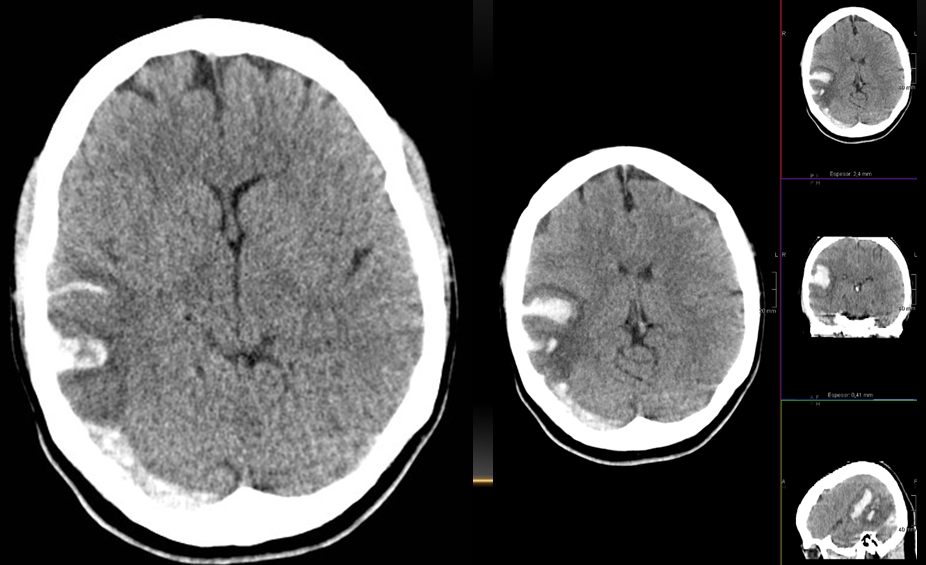

Paciente de 46 años de edad, asintomático. Se le realizo TC debido a traumatismo, posterormente se amplio estudio mediante RM.

En TC sus características son variables, aunque general mente es más denso que el LCR; sus características dependen del grado de contenido proteináceo.